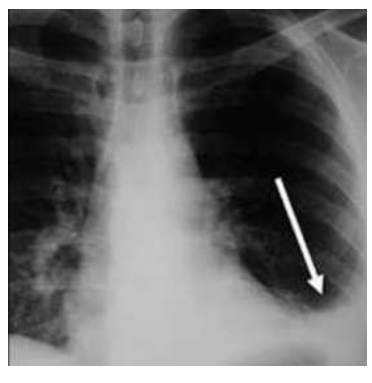

No raio X abaixo, verificamos opacificação do seio costofrênico esquerdo desenhando uma curva com a forma de uma parábola com a concavidade voltada para cima (seta). O nome deste sinal (curva) e o provável diagnóstico, respectivamente, são